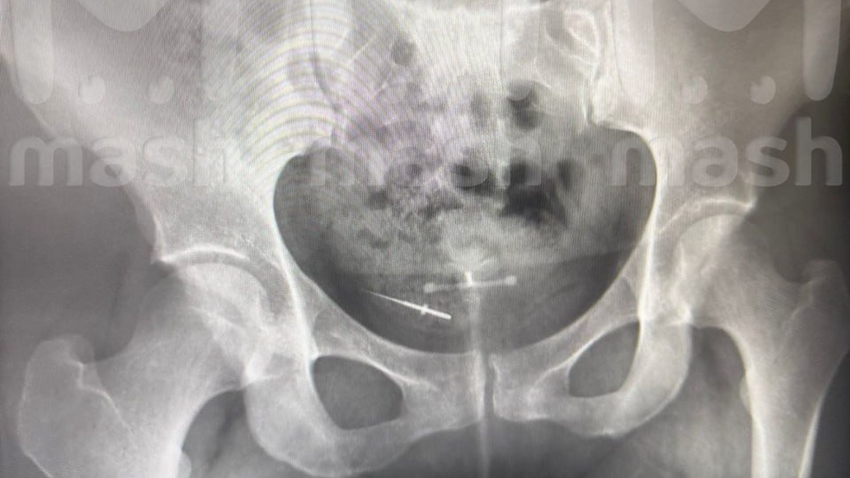

На рентгене стало видно, что в области таза у пациентки имеется иголка. Позже стоматолог заявил, что никаких инструментов не терял. В итоге пострадавшей девушке пришлось делать операцию, чтобы извлечь инородный предмет.